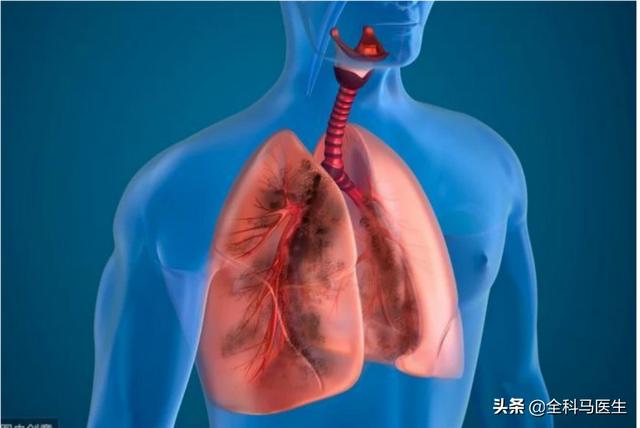

肺癌(lungcancer)、または原発性気管支原癌、原発性気管支肺癌は、気管支粘膜または腺から発生する肺の最も一般的な原発性悪性腫瘍である。組織学的病変により、小細胞がんと非小細胞がんに分けられる。臨床症状は、主に咳嗽、喀痰、喀血およびやせとして現れる陰性のものが多い。早期発見、早期診断、早期治療が予後を良くする!

肺がんは、他の悪性腫瘍と同様に、通常、肺がんの発生前や発生時には症状や徴候がなく、肺がんの初期段階では、痰を吐く、痰に血が混じるなどの症状がなく、肺がんが徐々に成長し、隣接する正常な組織や臓器に浸潤したり、圧迫したり、あるいは遠方からの転移が起こって初めて、肺がんの症状が現れます。

肺がんは肺の原発性悪性腫瘍の中で最も多く、主に気管支、細気管支、肺胞などに発生する上皮細胞腫瘍です。発見時にはすでに中期、末期になっている人が多いため、5年生存率は20%以下です。多くの人は肺がんが見つかったときにはすでに中期か末期になっているので、5年生存率は20%以下です。

肺がんは、肺の気管支や肺胞の粘膜にできる悪性腫瘍で、その発生には、長期の多量喫煙、特定の化学発がん物質への暴露、体の免疫力の低下などが関係している。特に、長期間大量の喫煙をしている成人の肺がんのリスクは、非喫煙者のそれよりもはるかに高い。したがって、非喫煙者や喫煙者は、できるだけ早期に禁煙することが肺がん予防のために非常に重要である。

肺がんの初期症状は、肺がんの発生部位の違いから、末梢型(肺の端に発生するがん)と中枢型(肺門近くの気管支に発生するがん)に分類される。末梢型肺がんの初期には、通常、明らかな症状はありません。中枢型肺がんは、しばしば気管支内腔に進展し、気管支内腔が狭くなり、無気肺や閉塞性肺炎を起こし、咳が続く、痰に血が混じる、胸が張る、息切れなどの症状が現れます。